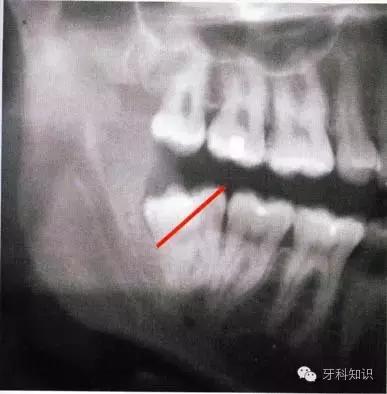

下牙槽神经阻滞麻醉(下颌孔注射)和舌神经、颊神经阻滞麻醉:(图5~5、5~6、5~7)。

术前观察阻生牙远中牙槽嵴的情况。图a中,可直接拔除;图b中,则需去除远中骨壁或分根

全颌曲面断层×线片。切割牙冠时应经过阻生牙远中面的牙颈部的釉牙骨质交界处